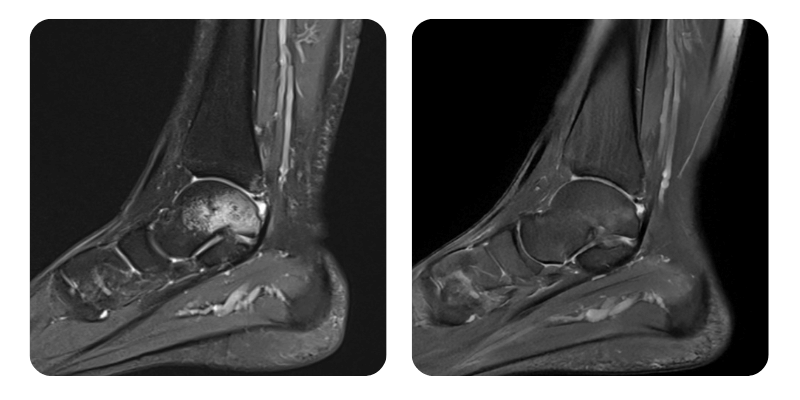

Înainte

După

B.A.A., 25 de ani - Edem osos post-contuziv la nivel talar stâng.

Diagnostic: Edem osos post-contuziv la nivel talar stâng, calcanean stâng, cuboid stâng și la nivelul maleolelor interne și externe stângi, Ruptură ligament talo-fibular anterior stâng, Edem la nivelul ligamentului talo-fibular posterior și la nivelul porțiunii profunde a ligamentului deltoid, Hidartoză.

Evoluție: S-a constatat o reducție a edemului de aproximativ 90%.